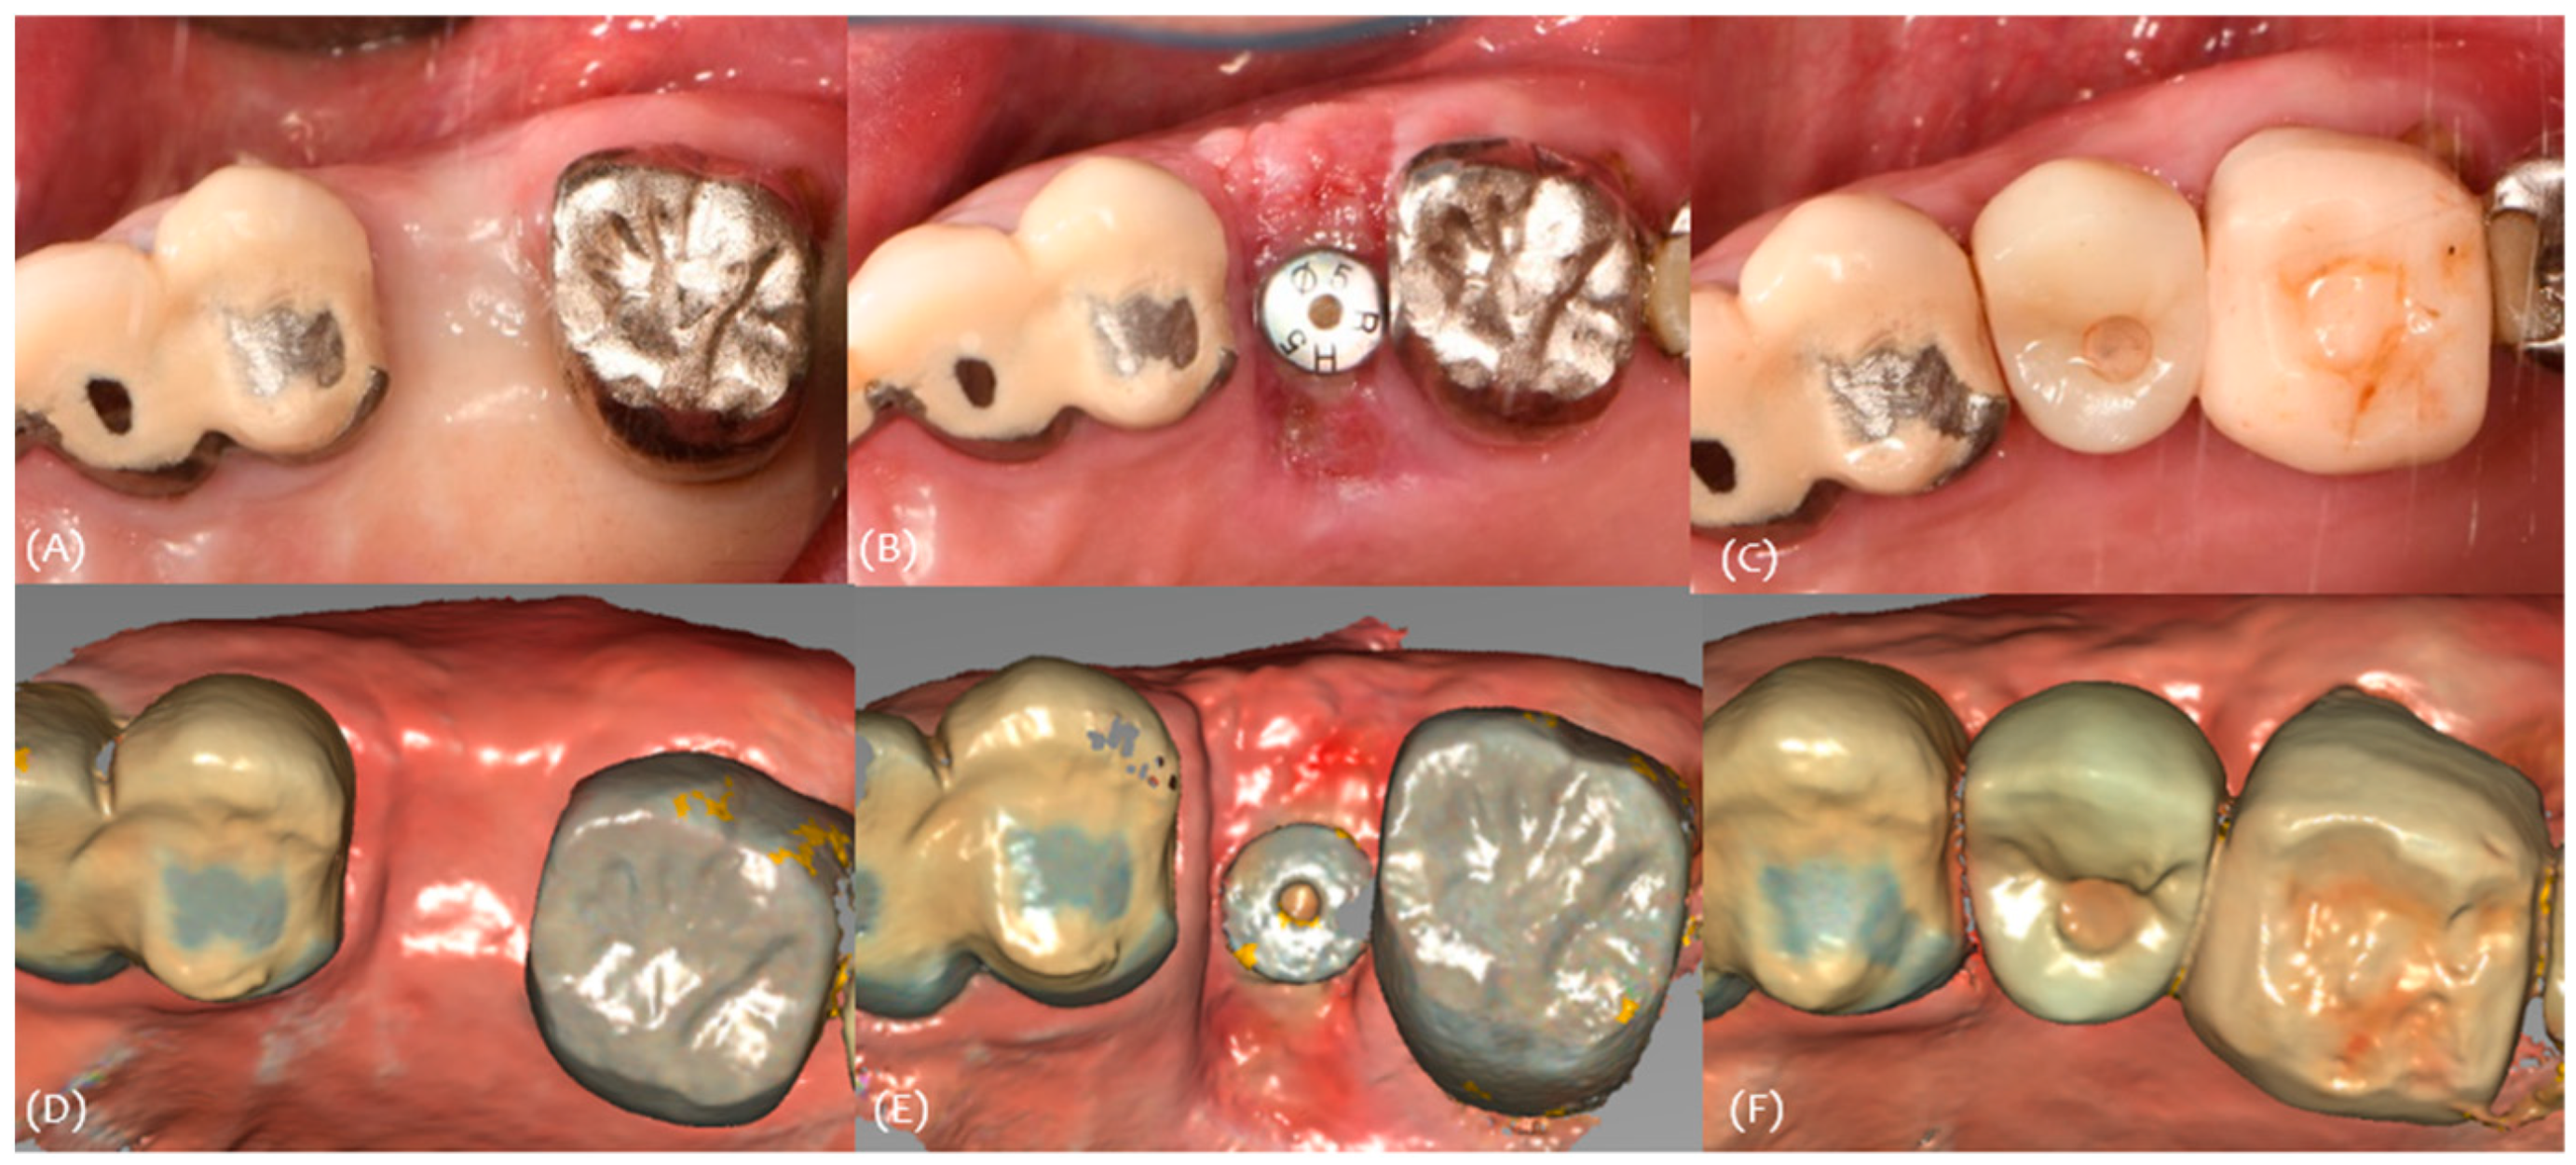

2.3. 3D Scan Protocol

- 2-week, 4-week, and 4-month intraoral scan after the surgery (CS 3600; Carestream Dental, Stuttgart, Germany) (Figure 2);

- In Exocad Software (exocad GmbH, DentalCAD 3.0 Galway, Darmstadt, Germany, 2021), a mesh file was added and superimposed using the adjacent teeth as a reference. By overlapping the recorded scan data using Exocad Software, cross-sections were set, and the increase in buccal soft tissue at fixture level was measured at five sites (mesial, mesio-middle, mid, disto-middle, and distal) and averaged.

3.3. Case 3

| #25i | #26 | #27 | |

|---|---|---|---|

| Classification (Seibert) | Class I | Class I | |

| Amount of maximum concavity (mm) | 1.2 | 0.8 | |

| Site | Pre-Op Concavity (mm) | Increased Buccal Soft Tissue Volume 2 Weeks After Op (mm) | Increased Buccal Soft Tissue Volume 4 Months After Op (mm) | |||

|---|---|---|---|---|---|---|

| #26i | #27i | #26i | #27i | #26i | #27i | |

| Distal | 0.8 | 0.4 | Δ 0.913 | Δ 1.43 | Δ 0.983 | Δ 0.52 |

| Disto-middle | 0.9 | 0.6 | Δ 1.22 | Δ 1.47 | Δ 0.695 | Δ 0.54 |

| Middle | 1.2 | 0.8 | Δ 1.18 | Δ 1.59 | Δ 1.01 | Δ 0.606 |

| Mesio-middle | 1 | 0.7 | Δ 1.4 | Δ 1.5 | Δ 1.03 | Δ 0.226 |

| Msesial | 0.8 | 0.5 | Δ 1.45 | Δ 1.34 | Δ 0.358 | Δ 0.467 |

| Average | 0.94 | 0.6 | Δ 1.2326 | Δ 1.466 | Δ 0.8152 | Δ 0.4718 |